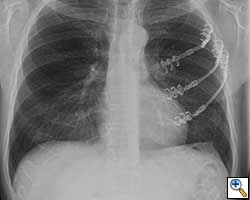

- Chest wall resection for malignancy (Figures 4-5)

| Figure 4: Model showing application in chest wall resection. | Figure 5: Postoperative chest x-ray showing the implants |